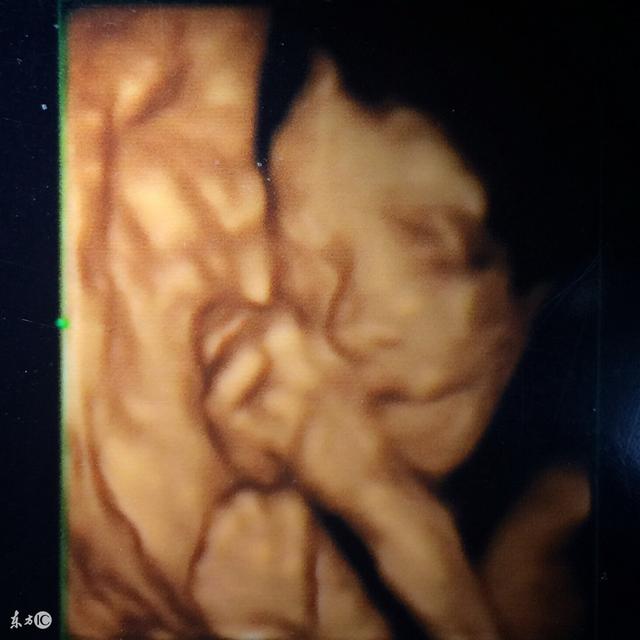

1、四维彩超的检查是在怀孕22-26周期间,通过做B超的方式检测胎儿的发育状况,能够检测到胎儿双顶径和胎儿的股骨长度,胎盘以及胎动、胎心或者胎儿的头部、肾脏、心脏、颜面部的发育状况。

说法四:四维图像里有玄机。

有孕妈说,有些机器是进口来的,在国外是可以提示性别的。所以,那机器照出来的四维彩超图像中会自动显示字母M或F,这个字母本身就是胎儿性别的缩写,M代表男孩,F代表女孩。

还有孕妈说,看孕囊的形式。孕囊是长条状的,就是男宝宝;孕囊圆圆的,就是女宝宝。